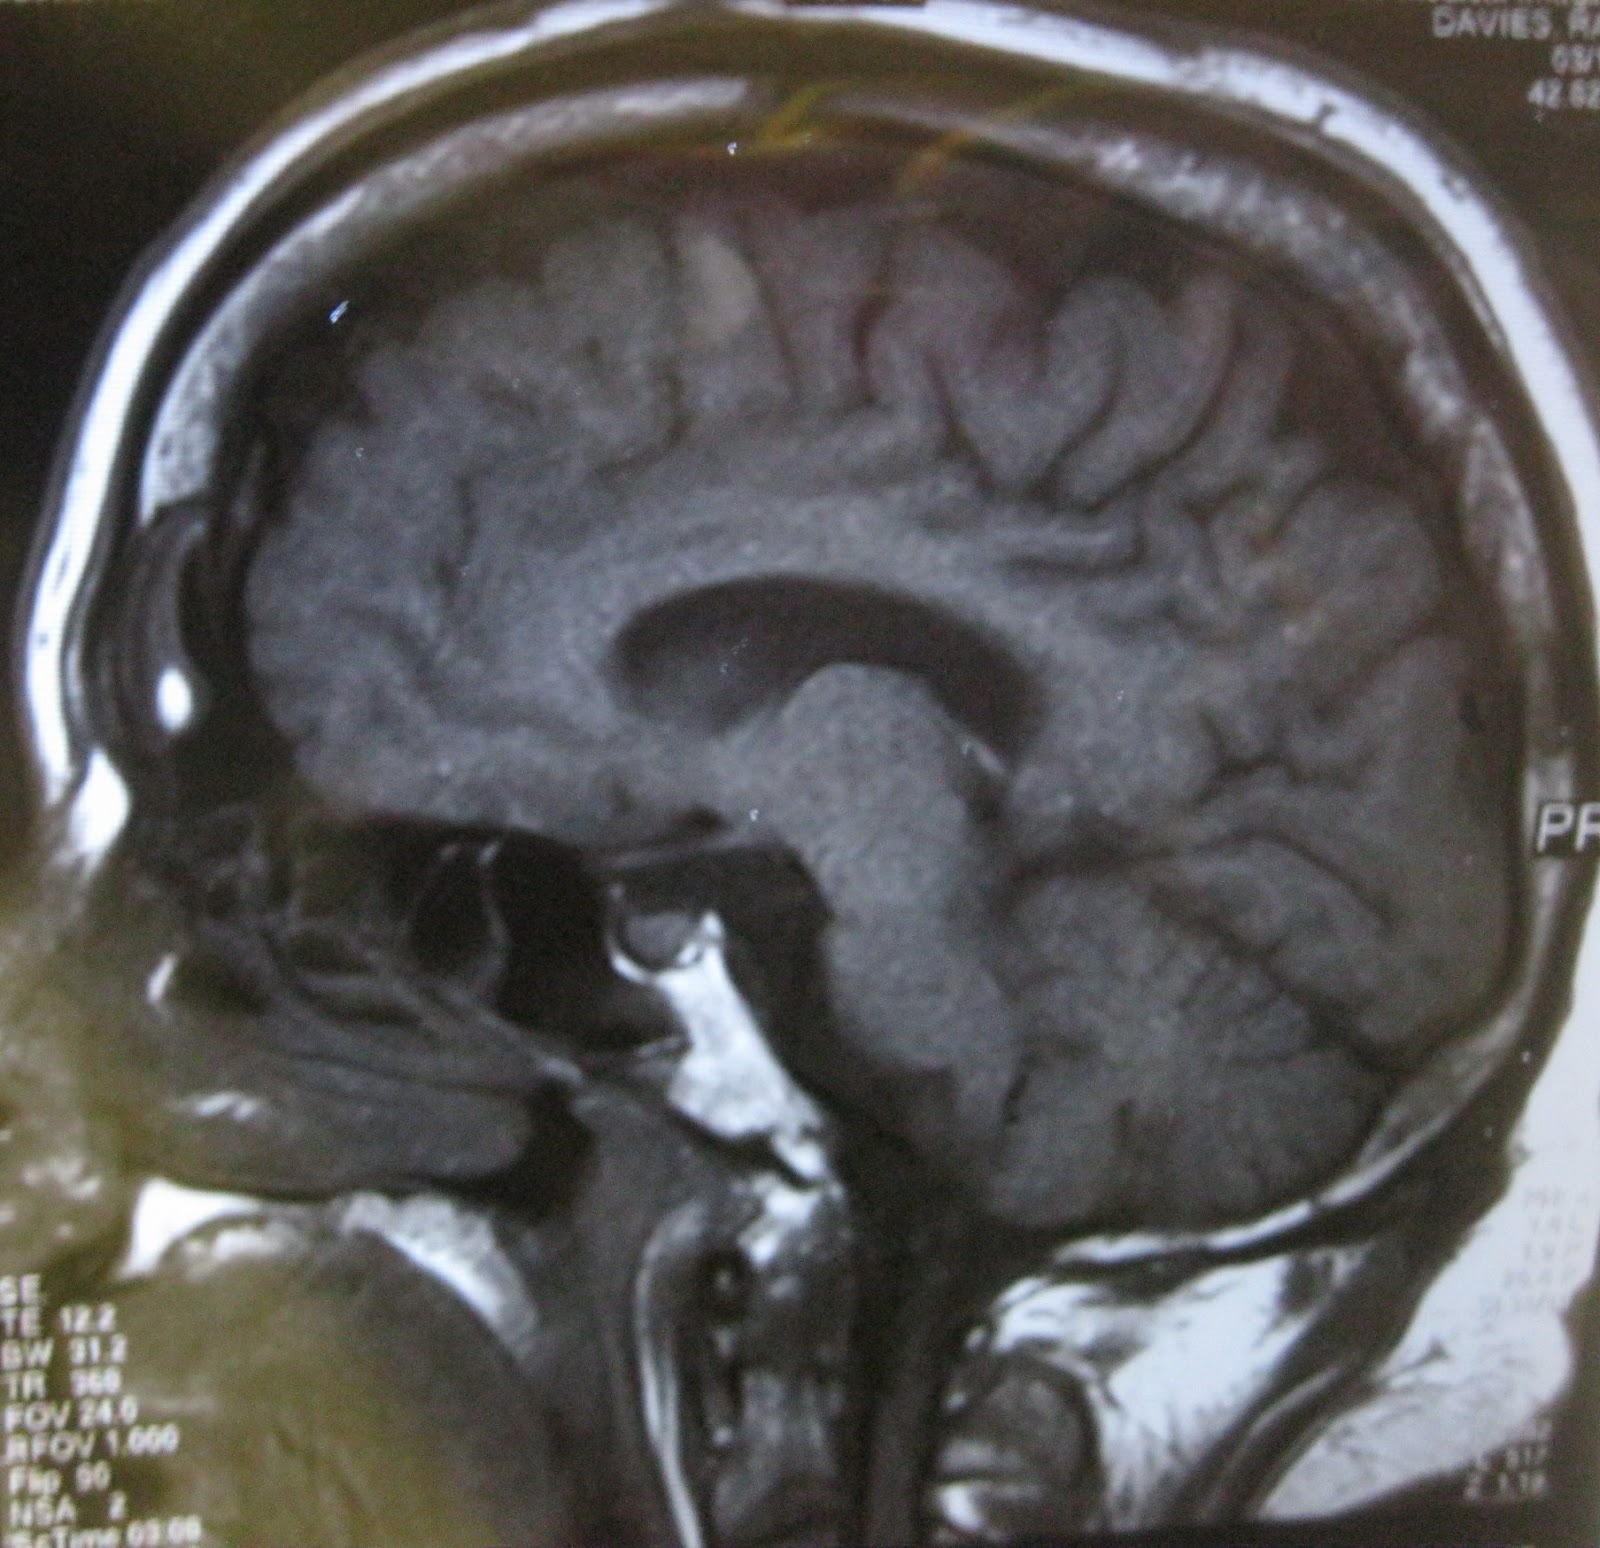

This...

...to this in seven days.

Sam apologises for the bad quality picture taken immediately after the plaster was removed. His camera was misbehaving today (22-04-2013). He'll have a new one to replace it tomorrow all going well.